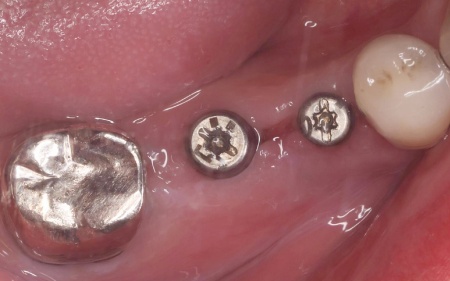

治療後